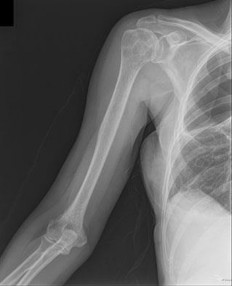

Question 12

A 13-year-old elite baseball pitcher presents with vague, insidious onset shoulder pain that is worst during the deceleration phase of throwing. He denies any acute pop or trauma. Radiographs reveal widening and lateral fragmentation of the proximal humeral physis compared to the contralateral shoulder. What is the most appropriate initial management?

Explanation

The patient is presenting with 'Little League Shoulder,' which is proximal humeral epiphysiolysis. It is an overuse injury caused by repetitive rotational stress on the open physis during the throwing motion. The mainstay of treatment is absolute rest from throwing, typically for 3 months, or until the patient is completely pain-free and radiographs show healing of the physis. Once healed, a gradual return-to-throw program focusing on pitching mechanics is initiated.